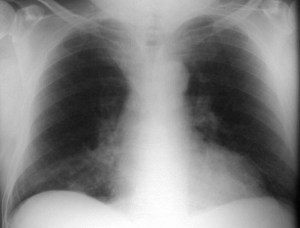

SIGNO DE LA ALTERACIÓN DEL CONTORNO AÓRTICO

La irregularidad, abombamiento o borramiento del arco aórtico en la radiografía de tórax en bipedestación o en decúbito supino, en un paciente con traumatismo torácico, obliga a descartar rotura aórtica como causa de dicha alteración. La flecha muestra el contorno aórtico anómalo. Además, hay un aumento de densidad en el hemitórax izquierdo correspondiente a derrame pleural –hemotórax en este caso-, que refuerza la sospecha de rotura aórtica.